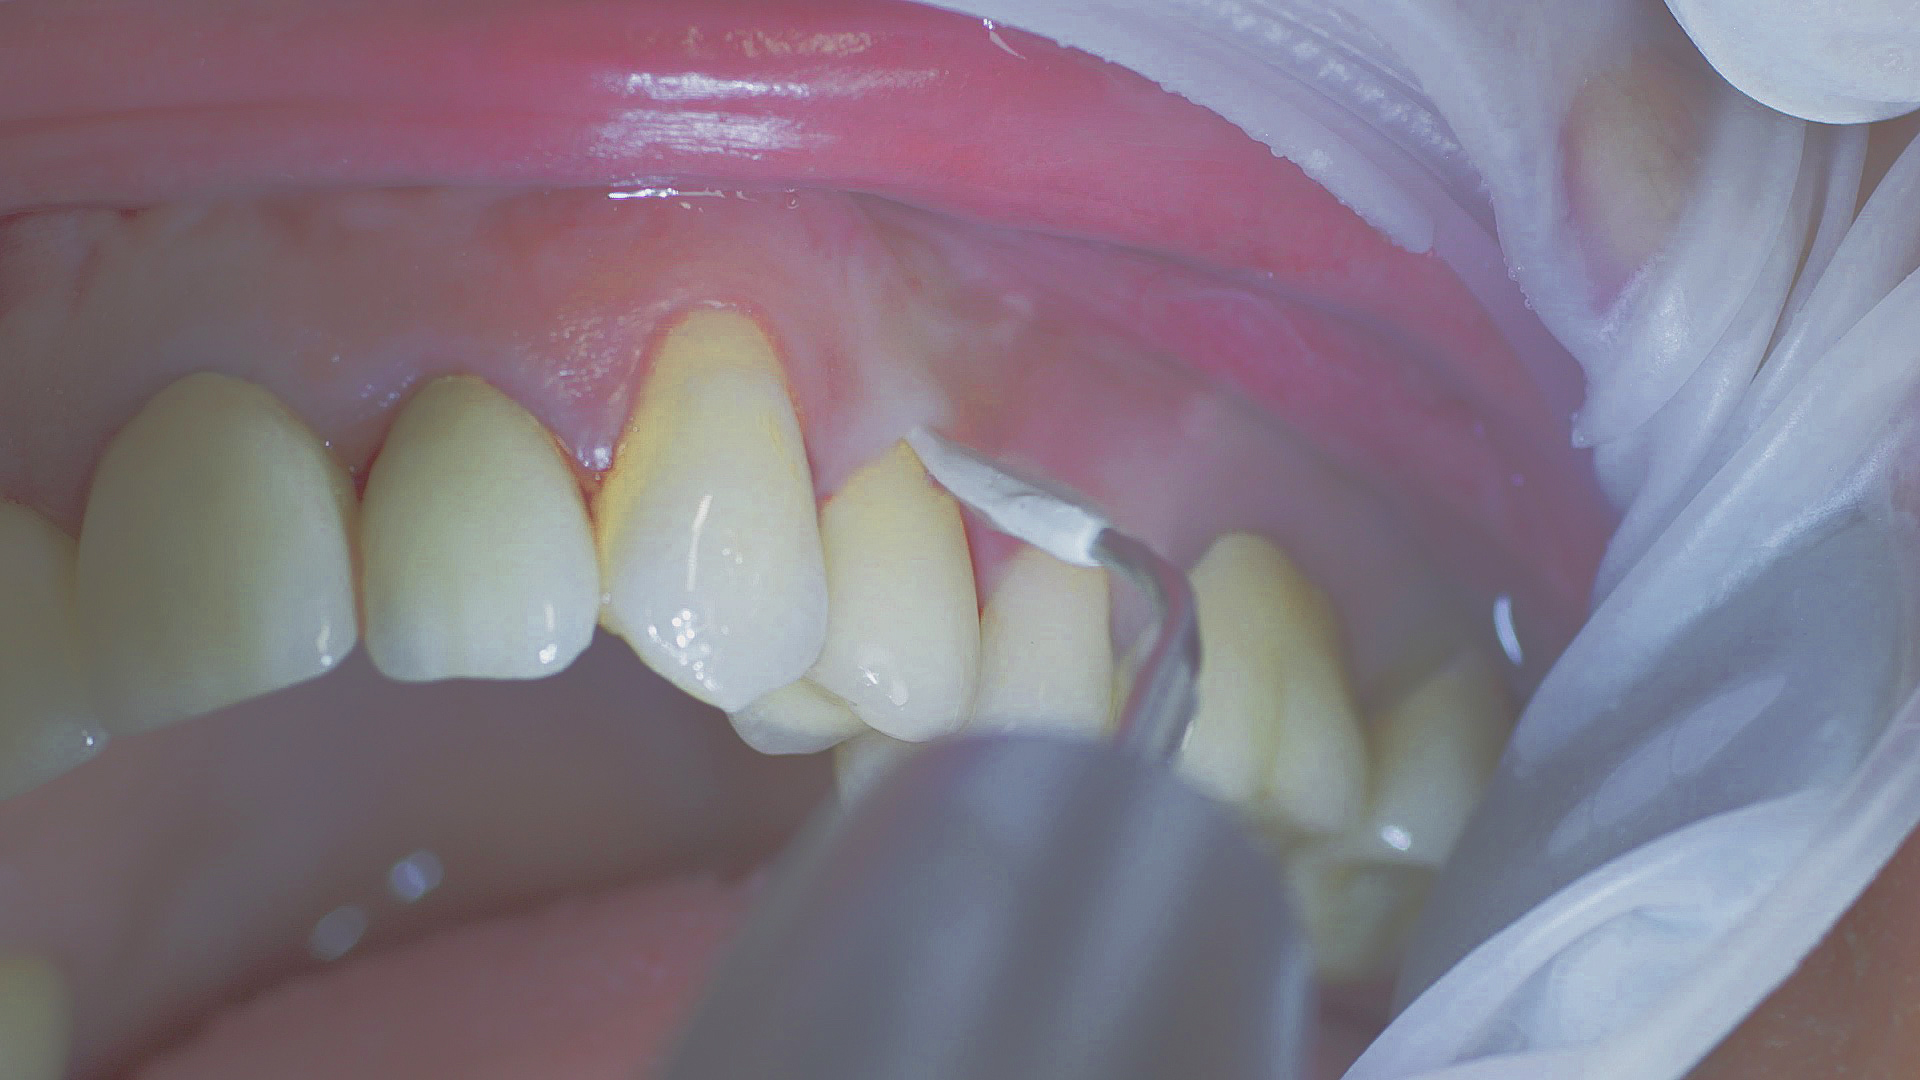

Tous les examens dentaires reposent sur l’étude des antécédents médicaux détaillés, associée à un diagnostic ciblé contenant le plus de détails possible. Le chirurgien-dentiste enregistre les facteurs de risque systémiques tels que le diabète ou le tabagisme et identifie toute augmentation de la tendance potentielle à l'inflammation.[3] Les tissus durs et mous sont examinés et les poches parodontales sont sondées dans le cadre d’un test de dépistage selon le PSR (Periodontal Screening and Recording). En cas de résultats anormaux, l’état du parodonte est ensuite enregistré et un traitement est démarré si nécessaire. Ce traitement débute par la gestion professionnelle du biofilm à l'aide par exemple de cupules rotatives et de composés de polissage (Fig. 1) et comporte des instructions complètes sur l’hygiène buccodentaire. Les systèmes à ultrasons restent une alternative ou un complément efficace aux instruments manuels pour le détartrage subgingival et la gestion du biofilm (présentation du Pr Dr Ulrich Schlagenhauf ;

Une bonne hygiène buccodentaire personnelle et une gestion professionnelle du biofilm, par exemple à l'aide de cupules et de brossettes, sont favorables à la santé parodontale et péri-implantaire.

Fig. 1 : Une bonne hygiène buccodentaire personnelle et une gestion professionnelle du biofilm, par exemple à l'aide de cupules et de brossettes, sont favorables à la santé parodontale et péri-implantaire.